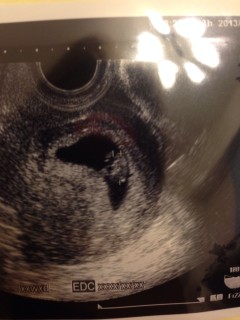

13年ぶりの妊娠♪どうしても欲しかった二人目チャン☆心拍確認で、ちょっと安心。CRL 1.41cm

8w0d

6wのときに血の塊がなん箇所かあるといわれた黒い部分も消えてて、大きくなってました♡人みたいな形に感動!

やっと赤ちゃんと、赤ちゃんの心臓が見れました!

小さくてもピコピコ動く心臓に感動しました☆

検診は、また2週間後!もっと成長してね(*^_^*)